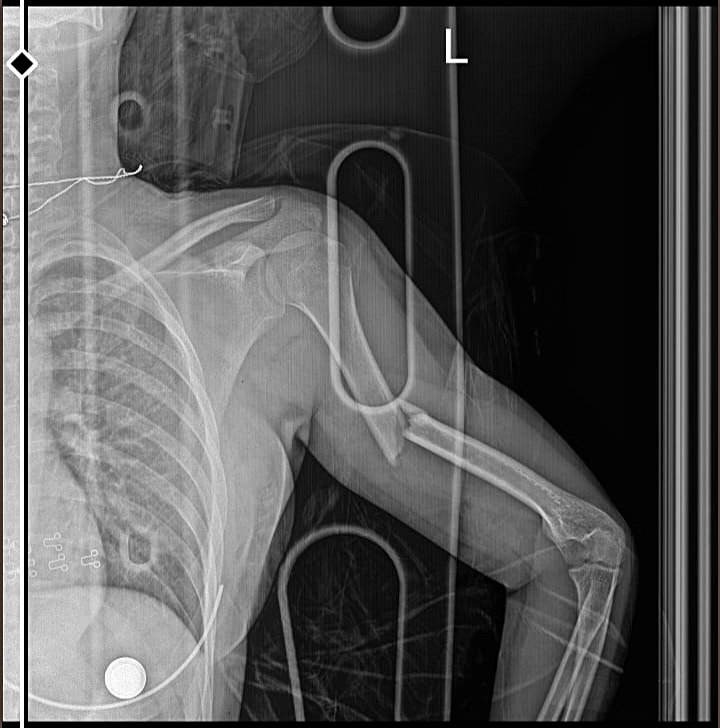

Aslında kendim için sordum, bundan 10 ay önce araba çarpması sonucu kolum 3 ayrı yerden kırıldı ve ameliyat olmam gerekti, 4 vida ve humenus çivisi var, kolum için fizik tedavi bile gerekti ama 10 ayın ardından hala acıyor, bazen kaldırdığımda, bir şey taşırken yada durup dururken. Eski halini alıcak mı yoksa ara ara kendini hissettiricek mi?

Arkadaşlarımla maç yaparken düşme sonucu kolum radius ve ulna kemiğinde toplam 8 kırık oluştu ilk doktora gittiğimde kırık olan kolumu düzeltti ler düz yaptılar yani zig zag olmuştu kolum sonra risk olmasına rağmen ameliyat olmamıştım 1 ay felan durdu öyle kontrole gittim ve kullanamazsın kolunu günlük hayatında zorlanma olur dediler tel koyup düz yaptılar titanyum tel bu tel dirsekten bileğe kadardı yaklaşık 1,5 ay durduktan sonra çıktı tel ve kolum eskisi gibi şuan